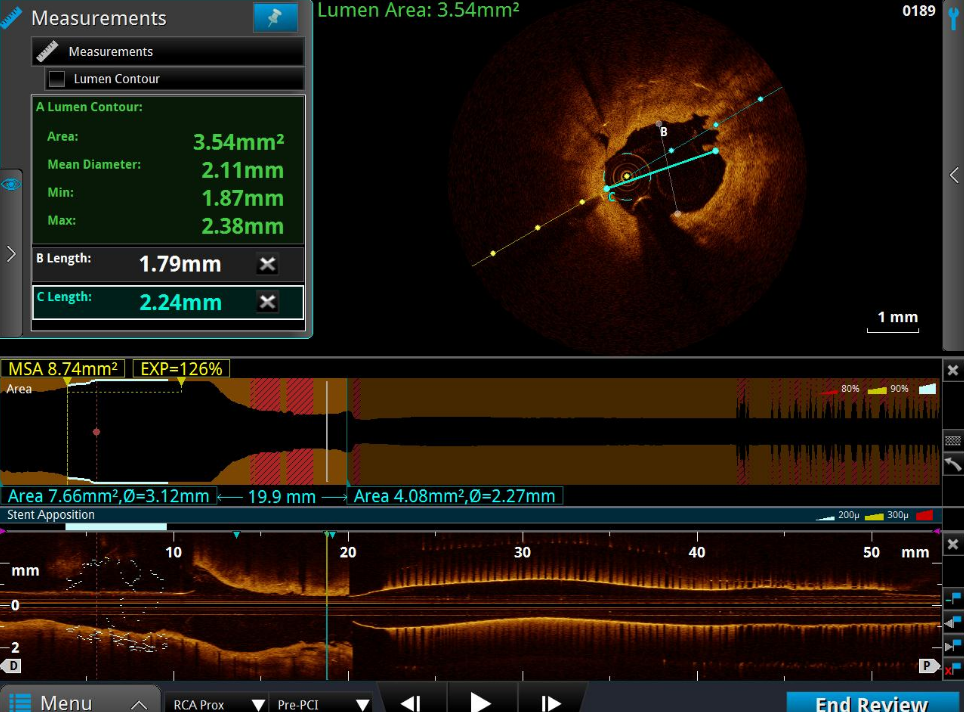

RCA—OCT术前检查

右冠开口ISR,最狭窄平均直径2.11mm;管腔面积 3.54mm²;以纤维斑块为主。

RCA—OCT术后检查